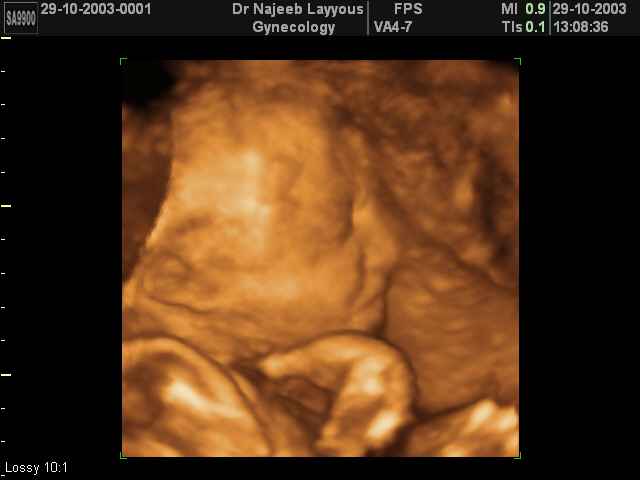

صور جانبية لرأس الجنين بجهاز الالتراساوند ثلاثي الأبعاد | الدكتور نجيب ليوس